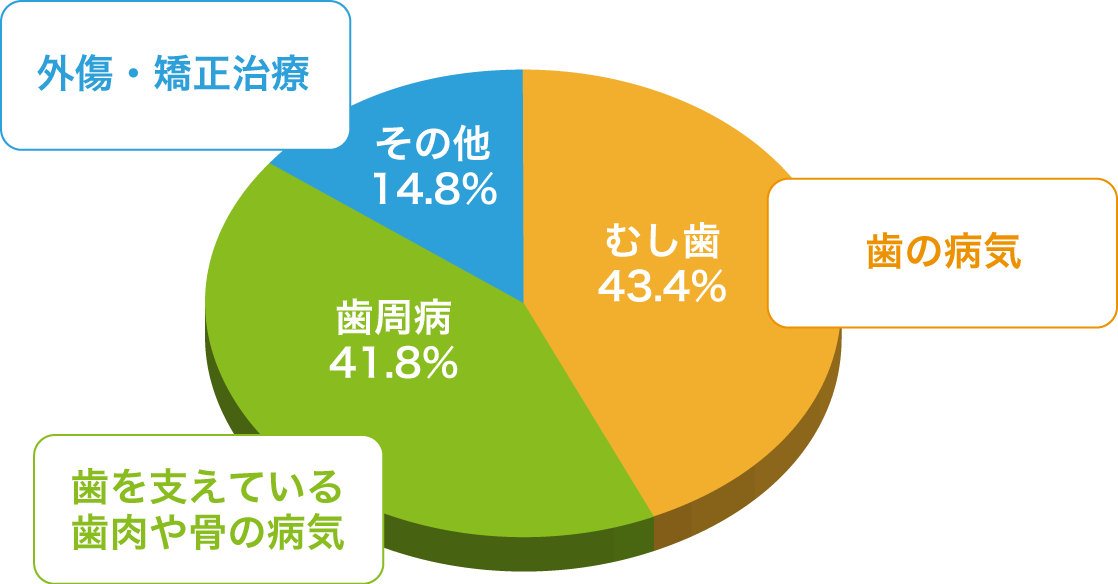

■歯なくす原因の約半数が歯周病によるものです。

歯周病はお口の中だけの病気?

■歯周病で引き起こされる病気があります。

歯周病菌で引き起こされる病気

糖尿病・細菌性心内膜炎・心筋梗塞・血管障害・誤嚥性肺炎・早産・未熟児出産等